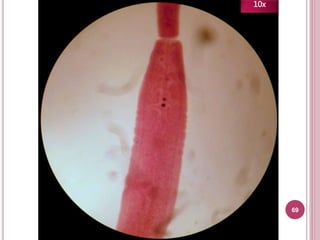

10x

Características

 Útero sacular

 Poro genital anterior